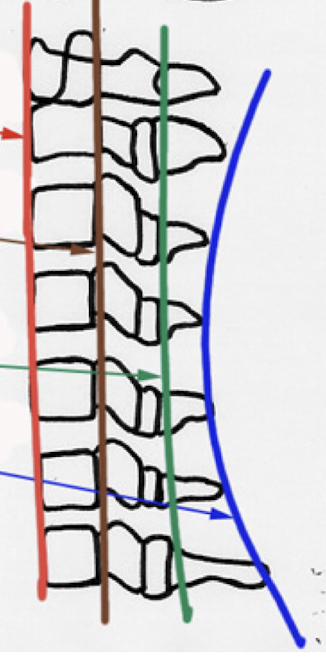

Label these 4 Lines? (C/S)